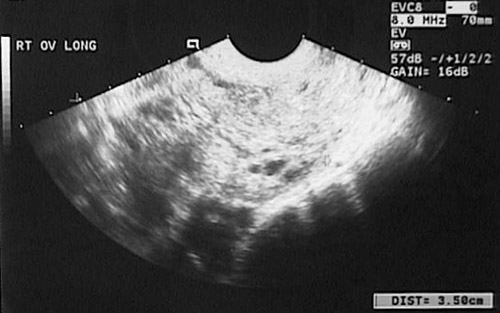

The cystic spaces representing the grape-like villi of an invasive mole are seen in this ultrasound view of the pelvis.